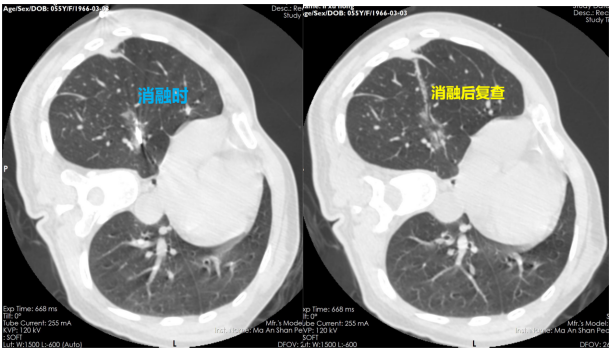

手術(shù)當(dāng)天,胸心外科手術(shù)團(tuán)隊(duì)在醫(yī)學(xué)影像科、麻醉科等科室的配合下,為李某進(jìn)行了微波消融手術(shù)。先由影像科技師進(jìn)行CT平掃,確定病灶位置及進(jìn)針的方向及深度,胸心外科醫(yī)生在李某體表定位點(diǎn)局麻后取一次性微波消融針逐層穿刺,CT再次掃描確保消融針到達(dá)準(zhǔn)確位置后用導(dǎo)線連接消融機(jī),選定恰當(dāng)功率,算好時(shí)間,開啟消融,同時(shí)術(shù)中給予心電監(jiān)護(hù)等監(jiān)測(cè),消融過(guò)程順利。消融后再次掃描CT可見(jiàn)消融范圍完全覆蓋右下肺結(jié)節(jié),手術(shù)治療成功!術(shù)后幾日復(fù)查CT,可見(jiàn)李某的肺結(jié)節(jié)變成“條索影”了,原來(lái)的結(jié)節(jié)已經(jīng)完全消失!李某后續(xù)治療定期復(fù)查即可。神奇的手術(shù)讓李某非常激動(dòng),“不開刀也可以根治腫瘤,現(xiàn)在的科技真發(fā)達(dá),以后一定讓更多的“結(jié)友們”知道這個(gè)好消息!”